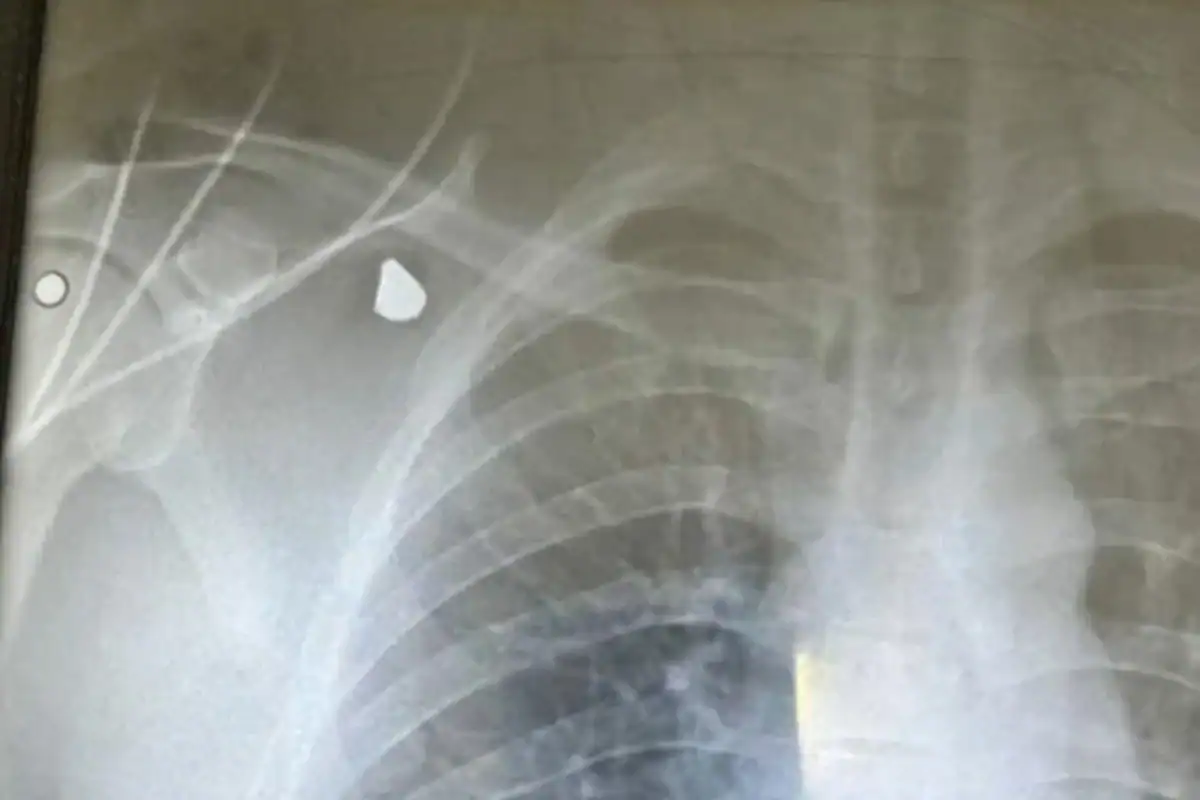

“Escutei dois disparos. Tinha um dançarino ao meu lado, peguei ele e empurrei para o chão. Quando fiz o movimento (para frente), o terceiro disparo atingiu minhas costas. Se eu ficasse assim (reto), poderia pegar do lado esquerdo do peito e poderia vir a falecer. Mas Deus foi bom e deu esse livramento a mim”, afirmou.

Em seguida, o cantor contou a sensação que teve: “Quando eu recebi o disparo, parecia um murro, um empurrão e um saco de cimento. Caí pra frente e desequilibrei”, detalhou, relatando que foi acalmar outra dançarina.